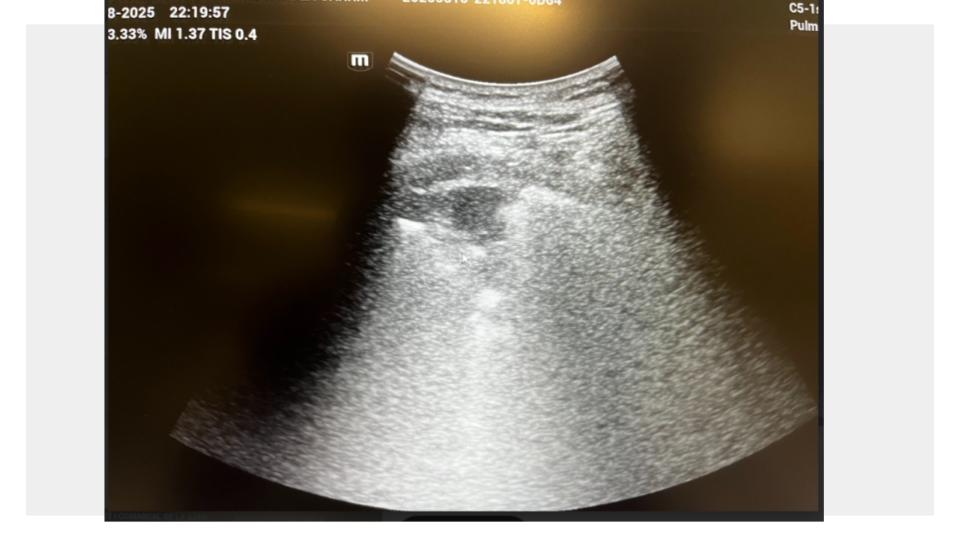

Se realiza ecografía pulmonar a pie de cama, donde se objetiva: consolidación subpleural en lóbulo inferior derecho, compatible con neumonía.

Se inicia tratamiento antibiótico dirigido por sospecha de neumonía neumocócica de la comunidad, sin necesidad de hacer otras pruebas diagnósticas que irradian o de derivar al hospital. Diagnóstico y tratamiento precoz en patología incipiente que puede tener evolución rápida y tórpida